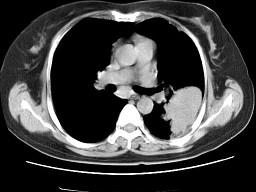

问题 女,52岁,左侧背痛一月,胸部CT如图,最可能的诊断为 ( )

选项 A、左肺炎性假瘤 B、肺隔离征 C、左肺周围型肺癌 D、左肺感染 E、左肺中央型肺癌

答案 A